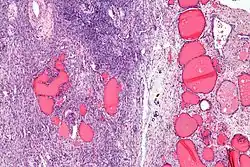

| Micrograph of a struma ovarii. Characteristic thyroid follicles are seen on the right, and ovarian stroma on the left. H&E stain. | |

A struma ovarii (literally: goitre of the ovary) is a rare form of monodermal teratoma that contains mostly thyroid tissue, which may cause hyperthyroidism.[1]

Low magnification -